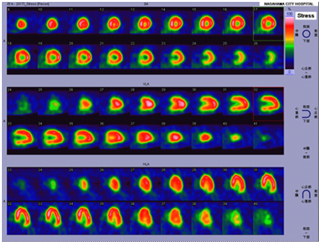

核医学装置

心筋SPECT